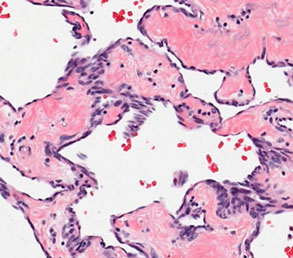

Micro: cords / small nests of round endothelial cells c lots of reddish cytoplasm that expand the vessels as they extend centrifugally from the lumen to the soft tissue in myxoid / mucinous sclerotic background

- blister cells c red cell fragments, which are tumor cells trying to form vascular lumens (similar to what may be seen in lobular breast ca)

-- can have vacuoles in lots of vascular tumors (blister cells are NOT specific for EHE) with plump endothelial cells

- usually does not make well-formed infiltrating vascular channels (like angiosarcoma does); good to distinguish from angiosarc

- lumen filled c necrotic debris, tumor and dense collagen

- round and possibly indented nuclei c intracytoplasmic vacuoles

- minimal mits, atypia or necrosis; though can be significant in small subset